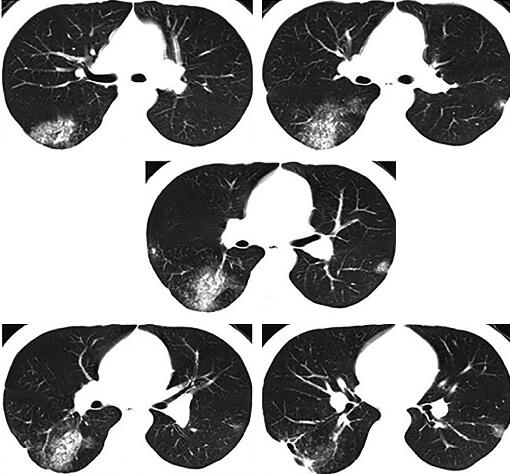

4天后热退,复查血常规白细胞计数及中性粒细胞百分比均恢复正常,治疗似乎有效,但此时患者出现咳铁锈色痰,偶有新鲜血痰,2013年2月27日复查胸部CT示右下叶后基底段原斑片影吸收,但背段有新发小片状阴影,带有小空洞,外基底段病灶也出现多发小空洞(图2),此时本该引起警觉却被“体温下来是硬道理”给冲昏了头脑,关键症状咯血也想当然的用肺炎解释了,治疗上联合左氧氟沙星氯化钠静脉滴注以加强抗感染治疗,2013年3月5日复查胸部CT(图3)可见右肺下叶背段病灶较前缩小,而外基底段斑片状渗出影较前明显吸收,更让医生坚定了肺炎的诊断。但此时的病人仍有气短(仅活动时)和轻度胸痛,咯血有加重倾向,最多一次量约5ml,呈鲜红色,这时医生感到困惑了。

图2

图3